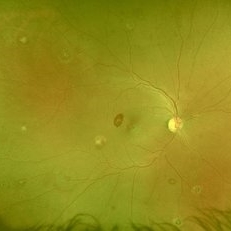

AZOOR

Sep 25 2025 by Hemanth Murthy, MBBS, MD, FASRS

OCT image of right eye of a 72 yr male with history of progressive loss of vision and loos of field of vision more in right eye. It shows a tribunal pattern of outer retina loss

Photographer: Mr Veda Vyas

Condition/keywords: acute zonal occult outer retinopathy (AZOOR)